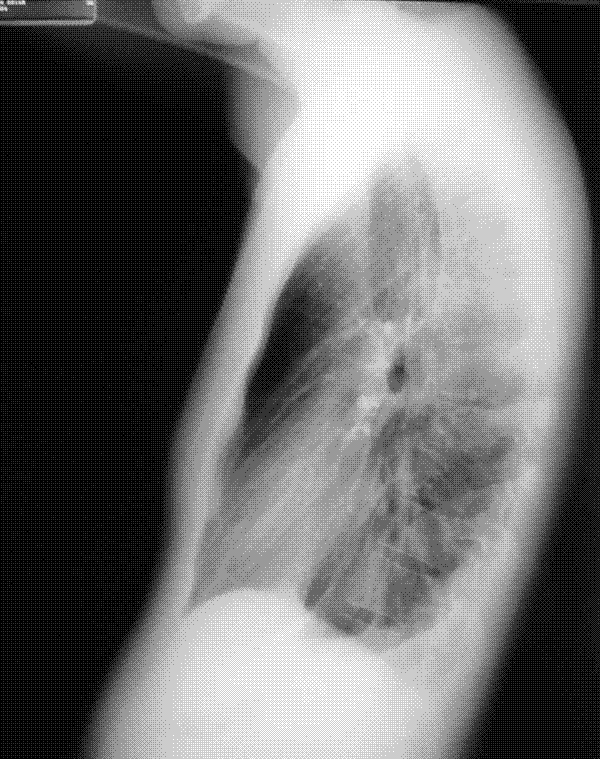

1. Lateral

1. 75-100 mL acúmulo en surco costofrénico- POST-> visible